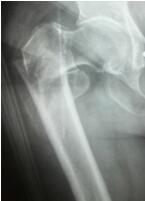

照片显示骨折位置 运用内固定手术后

高龄老人轻轻一摔,摔成了髋部骨折 不久前,家住泸州市江阳区三号信箱附近的薛大爷在家门口散步时不慎摔倒。“我们都以为只是普通的摔跤,以为只要休息一下就没事了。”薛大爷孙女薛女士说,让她和爷爷都没有想到的是在摔倒的第二天早上,薛大爷的右髋部疼痛不止,躺在床上连动都不能动了。家里人都慌了,赶忙拨打120,将其接送到了市中医院治疗。经急诊照片显示为右股骨粗隆间骨折(髋部骨折的一种),收入骨伤三科住院治疗。医生建议立即进行手术治疗,不要拖。

微创切口+“半瓶墨水”出血量,手术台上,患者为医生“点赞” 当天下午,在医院麻醉科等科室的高效配合下,由吴东海主刀,为老人实施微创下的右股骨粗隆间骨折闭合复位PFNA(股骨髓内钉)内固定术。

术中,在X线机透视下,手法准确复位——切开几个小口植入PFNA——将骨折固定稳定——缝合切口。这一系列动作一气呵成,手术仅用时20分钟,手术切口总共5针,出血量很少,仅有差不多半瓶墨水的出血量,全过程只有轻微注射穿刺的疼痛。医生高效、精准的手法,赢得了患者的称赞。在手术结束时,薛大爷竖起双手大拇指为医生的精湛技艺比赞,医生也为乐观、勇敢的薛大爷比赞。这一幕温情默默地流淌在手术间,让原本让人觉得冰冷的手术间不再冰冷。